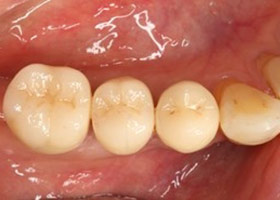

假牙完成照

因植牙恢復正常咬合